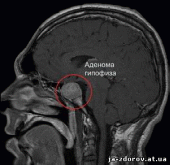

Магнитно-резонансная томография. Наиболее информативный метод исследования гипофиза. При магнитно-резонансной томографии визуализируются передняя и задняя доли, воронка гипофиза, возможно оценить симметричность гипофиза, положение воронки, состояние спинки турецкого седла. На МР-сканах структура аденогипофиза гомогенная, изоинтенсивна с белым веществом мозга.

Аденомы гипофиза на Т1 ВИ – визуализируются как зоны со сниженным по сравнению с остальной тканью аденогипофиза сигналом, на Т2ВИ – как зоны с повышенным сигналом. При внутривенном контрастировании аденомы накапливают контрастное вещество и можно более детально оценить структуру опухоли.

Рисунок Магнитно-резонансная томограмма головного мозга в коронарной плоскости: аденома гипофиза